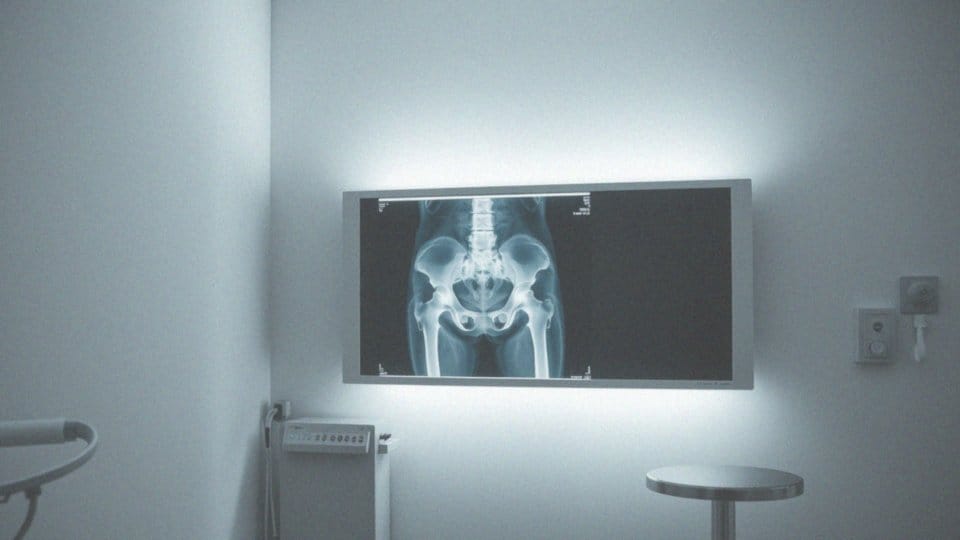

RTG stawu biodrowego to nieinwazyjna metoda diagnostyczna, która bazuje na promieniowaniu rentgenowskim. Jej kluczowym celem jest analiza struktur kostnych stawu biodrowego, w tym:

Dzięki temu badaniu lekarze są w stanie identyfikować różnorodne zmiany patologiczne. Przeważnie RTG wykonuje się w dwóch projekcjach:

- AP (anterior-posterior),

- osiowej Lauensteina,

RTG stawu biodrowego to cenne narzędzie, które dostarcza kluczowych informacji na temat budowy anatomicznej stawu. Lekarze, przyglądając się obrazom rentgenowskim, dokonują oceny struktury kości miednicznych, obejmujących m.in.:

- kość krzyżową,

- guziczną,

- talerz biodrowy.

Ponadto, nie zapominają o szczegółowej analizie kości udowych, w tym ich głowy i szyjki. Dzięki temu badaniu możliwe jest wykrycie różnorodnych zmian pourazowych, takich jak:

RTG stawów biodrowych jest przeprowadzane głównie w dwóch kluczowych projekcjach:

- AP, czyli antero-posteriornej, – przedstawia podstawową strukturę stawów biodrowych, obejmującą kość udową i miednicę,

- osiowej Lauensteina, – umożliwia dokładniejszą analizę szyjki kości udowej oraz panewki stawu biodrowego, co jest niezwykle istotne w procesie diagnozowania różnych patologii.